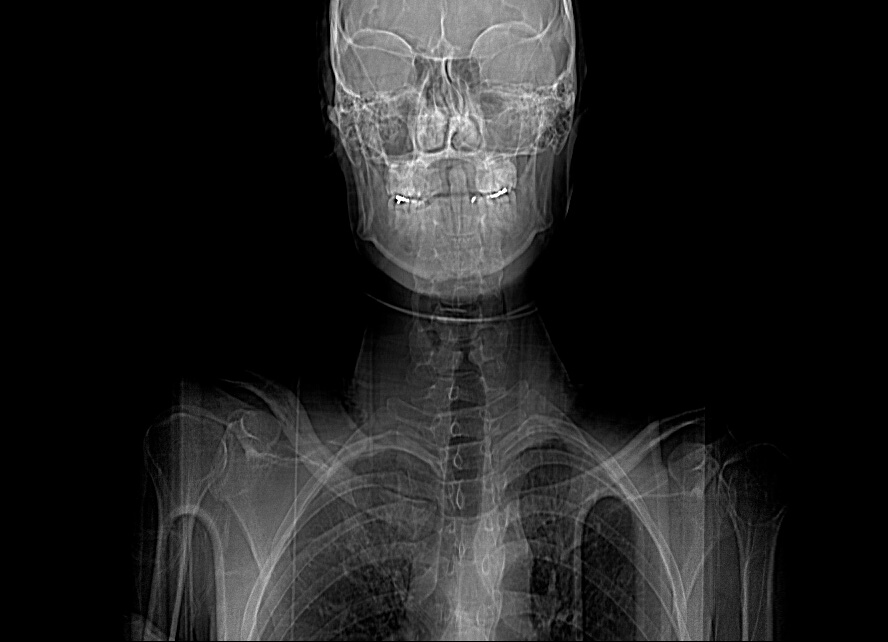

I will be the film composer for Rebecca Doppelt’s next film Bugbaby. I was on set today to get a head start by observing her directing, which was fun. I crashed my motorcycle on the way home, which was not. I was hospitalized with a serious concussion and I lost 24 hours of my memory, but I’m okay and the film is going to be great.